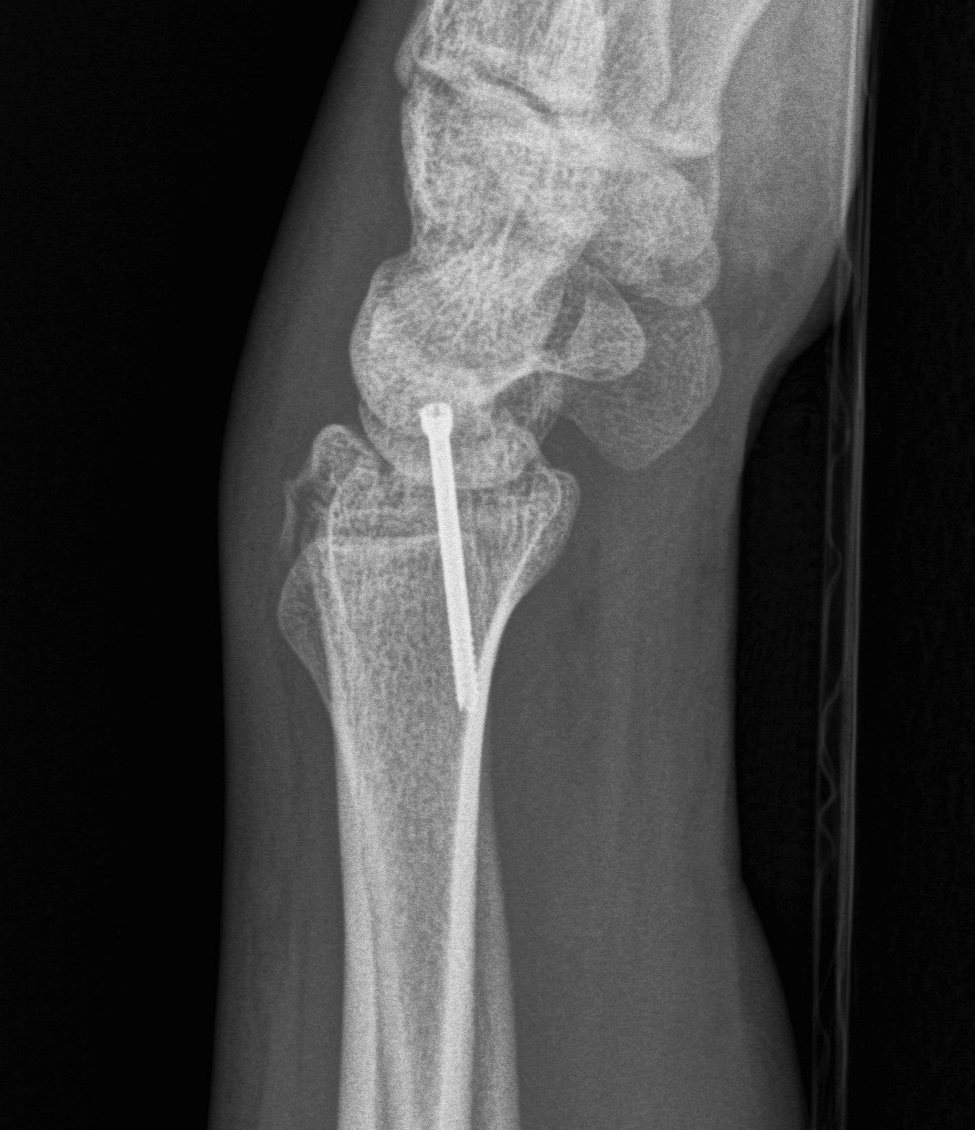

Distal Radius Fracture DRUJ incongruentDRUJ FractureDRUJ Fracture CT

Sigmoid notch disruption and DRUJ instability